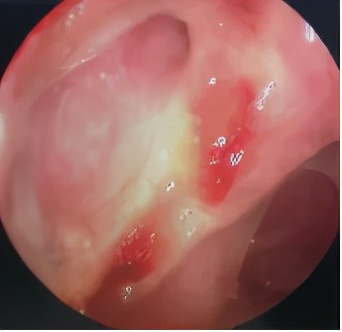

于是在全麻下为她做了手术,半小时就结束了,术后3天出院,复诊1年半,泪囊造口宽敞通畅,洪大姐再也没有溢泪。

术后内镜检查泪囊造口通畅